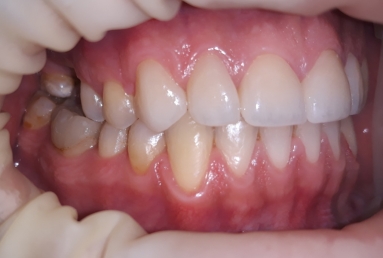

The final porcelain veneers for all frontal maxillary teeth are completed with tooth whitening and changing some composite fillings in lower frontals. On the lower left side a dental implant is inserted, on the upper right side external sinus lift is done. the treatment will be finalised with another upper implant, then two crowns on implants.